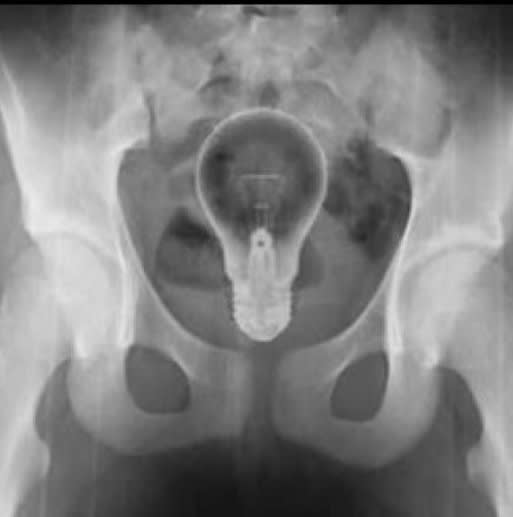

Rhôôôooo

Il (ou elle ?) a rentré l'ampoule par le mauvais bout ... pas étonnant !

Amha c'est un fake